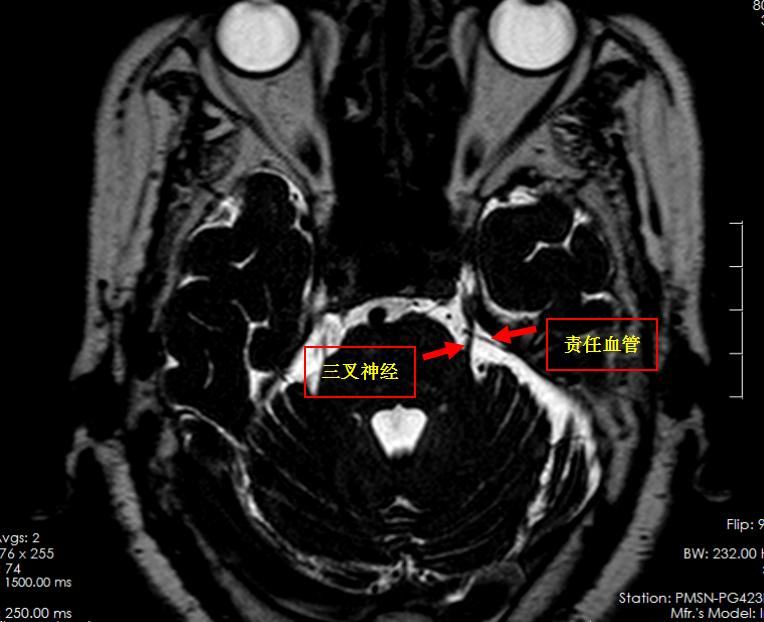

我院神经外六科主任吴杰接诊了患者。我院MR三叉神经薄层扫描提示:患者左侧三叉神经颅内段内侧缘小血管骑跨,左侧三叉神经局部受压左偏。经过详细问诊、查体后,考虑患者为三叉神经痛。吴杰为患者完善相关检查后,考虑到患者大剂量服用药物仍无法止痛,建议通过微血管减压术,为她解除病痛。

头颅术前MRI:左侧三叉神经颅内段内侧缘小血管骑跨,左侧三叉神经局部受压左偏。

术中,吴杰发现一根动脉血管正压迫三叉神经,这就是患者疼痛的原因。他轻巧地将动脉血管推移,并在血管和神经之间垫上一个棉片,解除血管的压迫。手术过程顺利。术后,林奶奶恢复良好,疼痛完全消失。